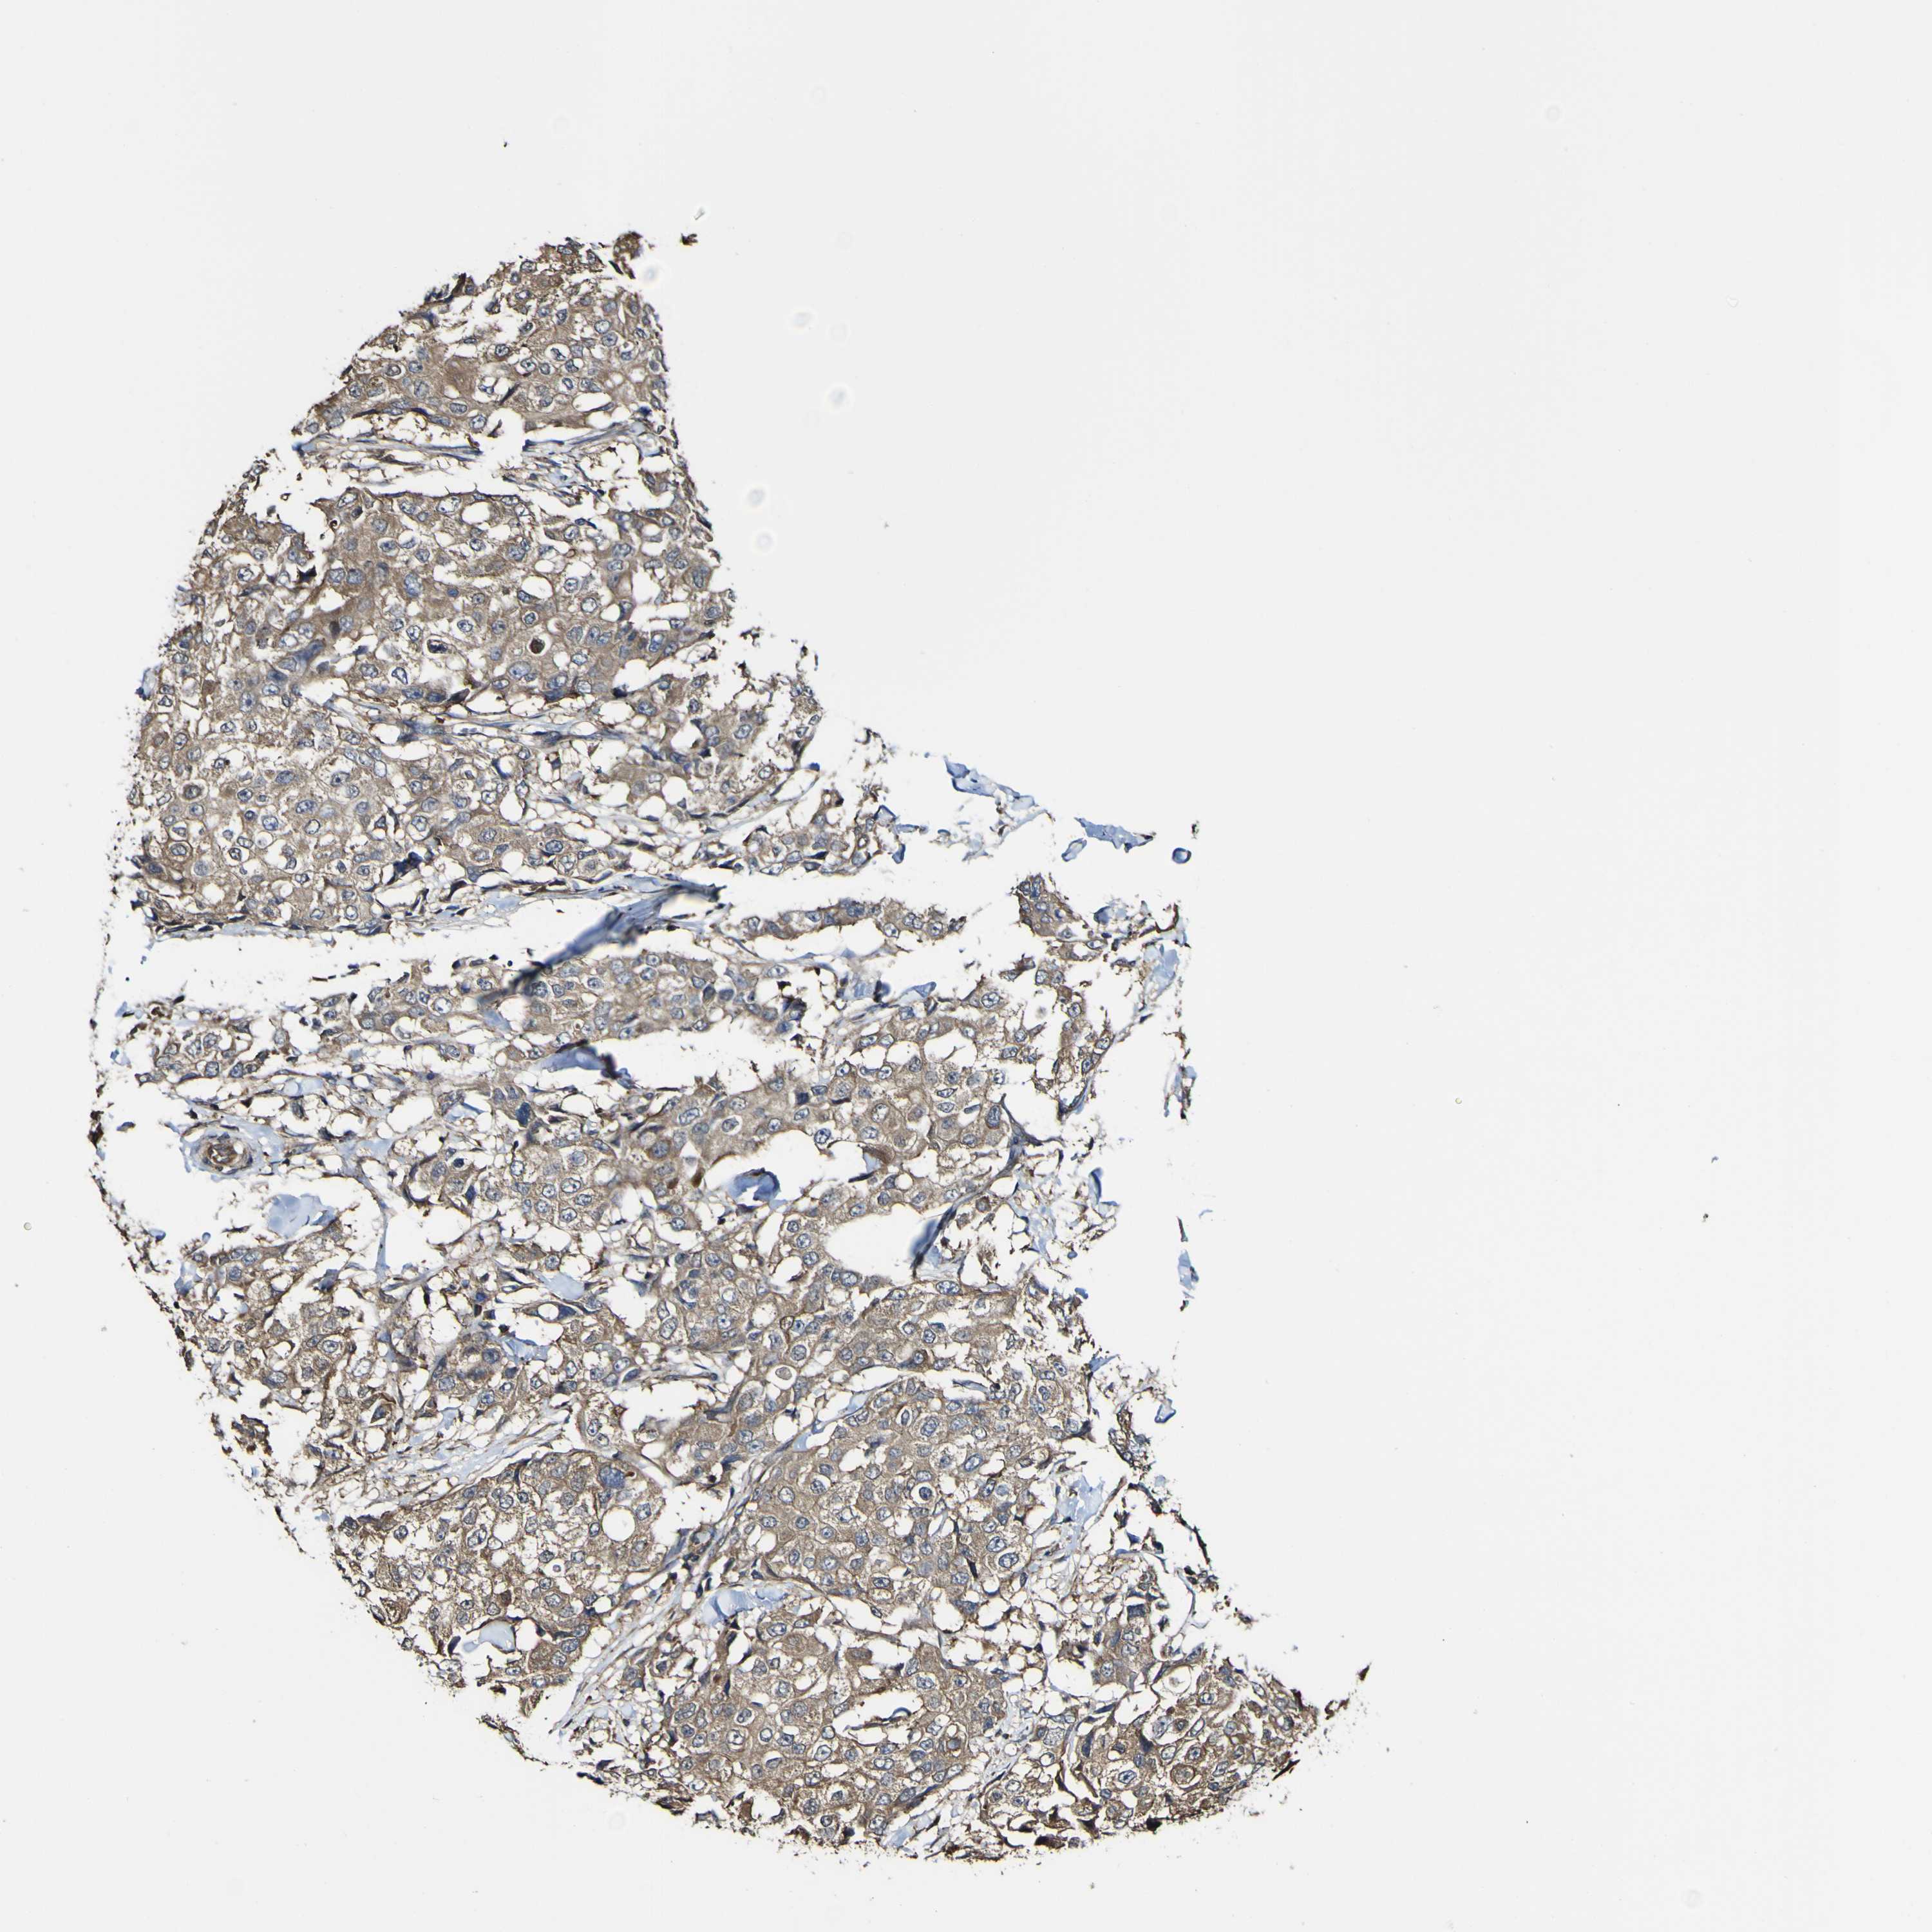

CANCER BREAST CANCER Show tissue menu

BRCA TCGA BRCA VALIDATION PROTEIN EXPRESSION